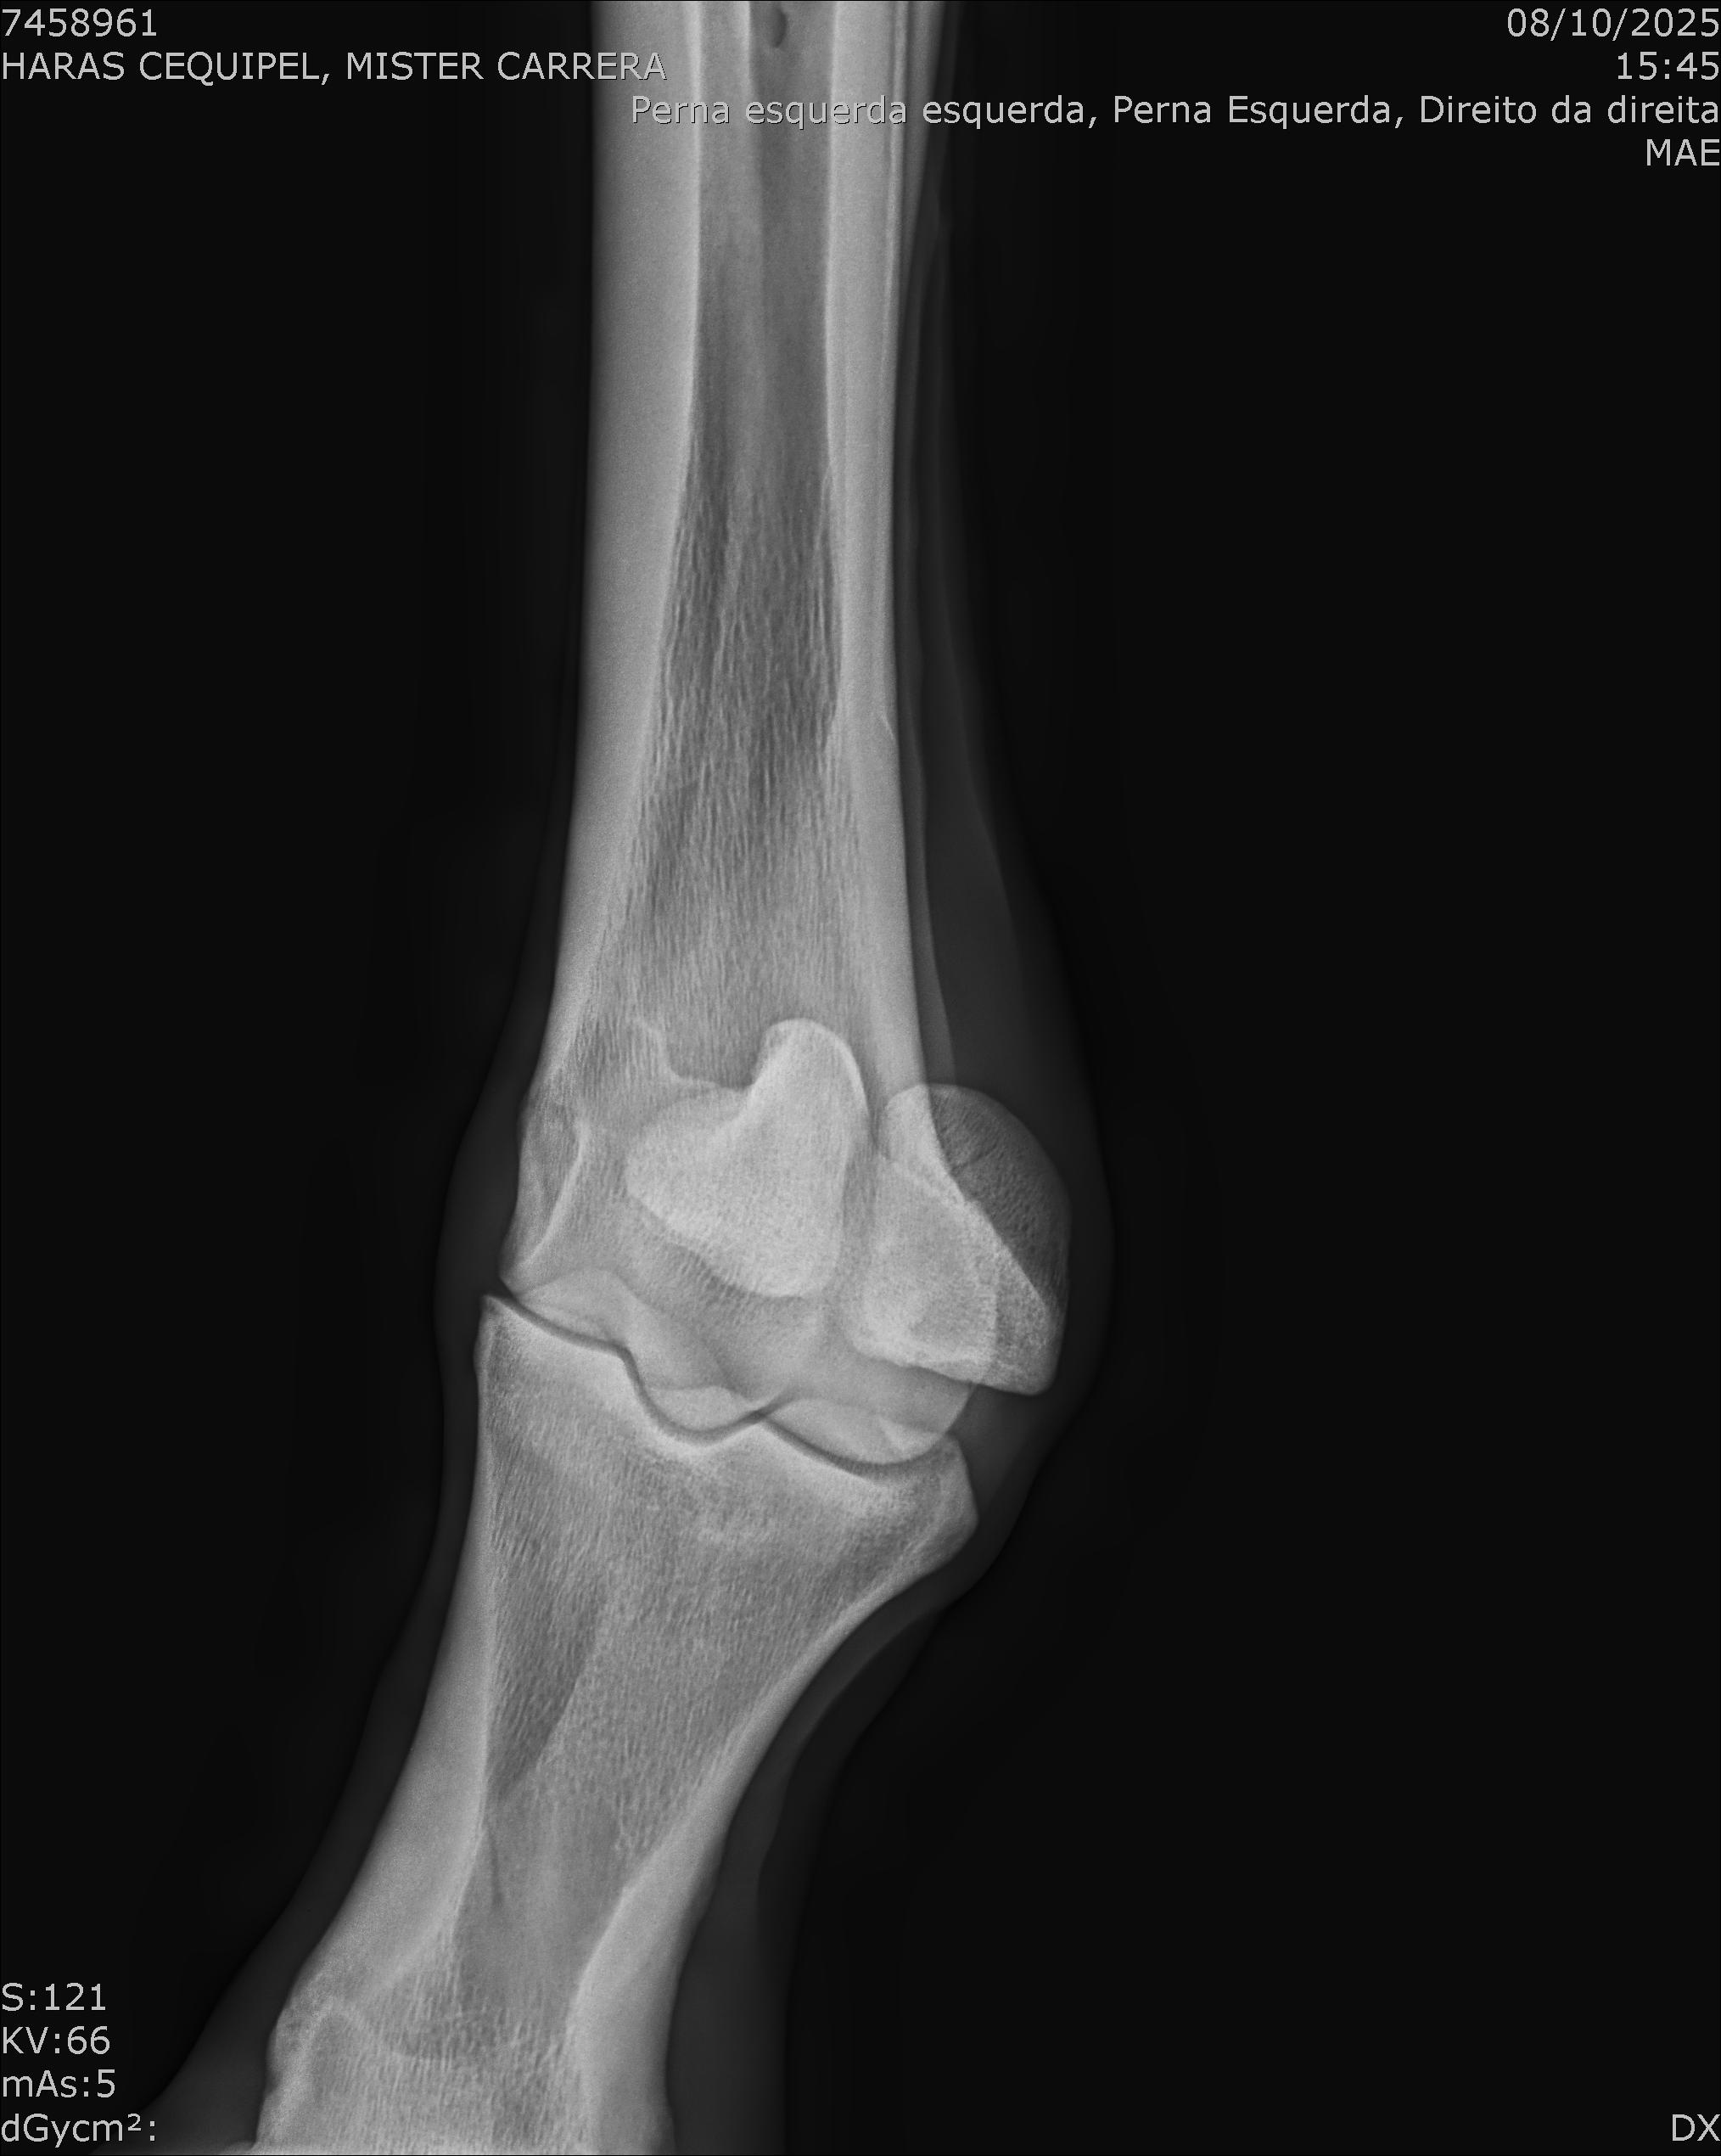

:: RAIOS-X DO LOTE